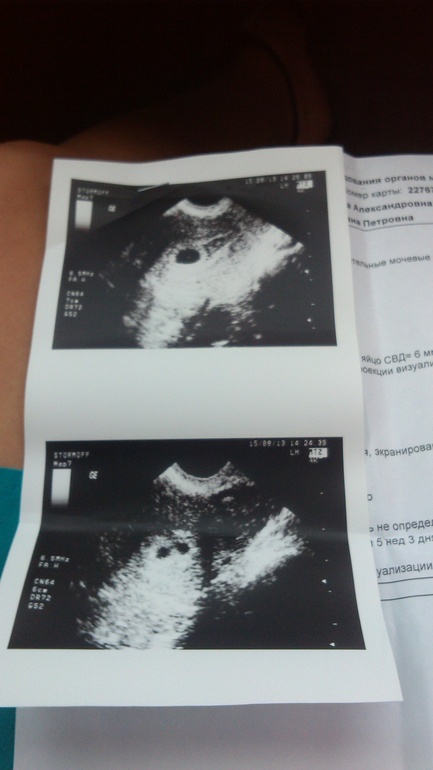

Вот так выглядели мои узи.

Врач: Один! Точно! 4 млм, срок по плоду 5 недель и 3 дня. Растет, все бьется!

Матка тьфу тьфу - никакого тонуса. Все в норме.